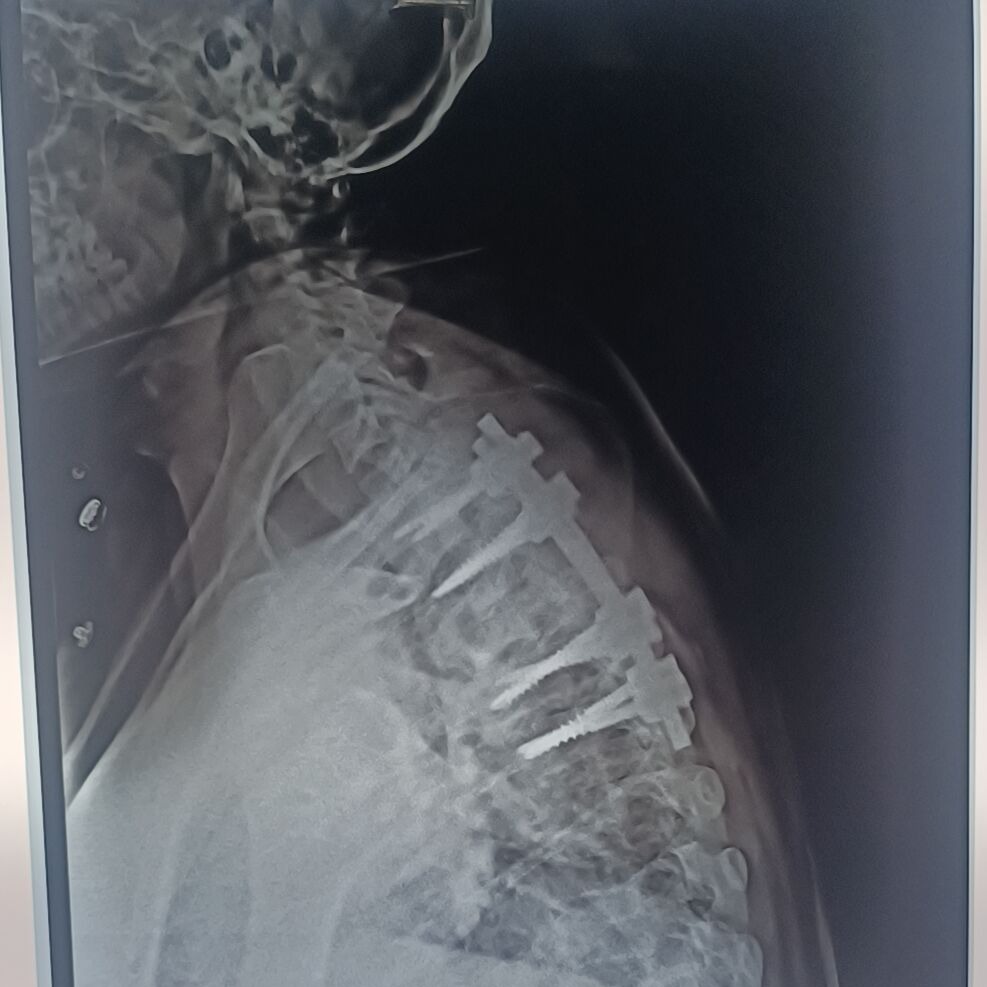

ARE YOU SEARCHING FOR SPINE SURGERY SPECIALIST IN PUNE ? SPINE SURGERY DOCTOR IN PUNE ? SPINE SURGERY SPECIALIST IN SHIVAJI NAGAR ? INFECTION SPINE TREATMENT IN PUNE ? TB SPINE TREATMENT IN PUNE ? MEET DR. NITISH AGARWAL BEST SPINE SURGEON IN PUNE, AUNDH, SHIVAJI NAGAR, DECCAN, KOTHRUD, ERANDWANE, DATTAWADI, SWARGATE, FC ROAD, KARVE ROAD TB SPINE / TUBERCULOSIS IN SPINE / KOCH DISEASE / INFECTION IN SPINE – COMPLAINTS :- A PATIENT CAME WITH COMPLAINTS OF WALKING IMBALANCE WITH DIFFICULTY IN STANDING OR WALKING PROPERLY. SEVERE UPPER BACK PAIN. BILATERAL LEG TINGLING, STIFFNESS AND HEAVINESS DIAGNOSIS :- D3 VERTEBRAL DAMAGE WITH EPIDURAL ABSCESS WITH SEVERE COMPRESSION OF SPINAL CORD. SURGERY :- D1 TO D5 SPINAL FIXATION SURGERY WITH TITANIUM SCREWS AND RODS WITH SPINAL CORD DECOMPRESSION WITH EPIDURAL ABSCESS DRAINAGE AND BIOPSY OF DEAD TISSUE AND SAMPLE IS SENT TO LABORATORY FOR EXAMINATION. RECOVERY :-THE PATIENT STARTED WALKING FROM DAY 1 AFTER THE SURGERY. HIS LEG PAIN , TINGLING , STIFFNESS REDUCED. ON BIOPSY REPORT TUBERCULOSIS INFECTION IS DIAGNOSED, SO WE STARTED MEDICINE FOR TB FOR 1 YEAR. AFTER REGULAR EXERCISES AND PHYSIOTHERAPY NOW HE CAN WALK PAIN FREE. HE IS NO LONGER FEELS ANY STIFFNESS OR TINGLING IN LEGS AFTER 2 MONTH OF SURGERY